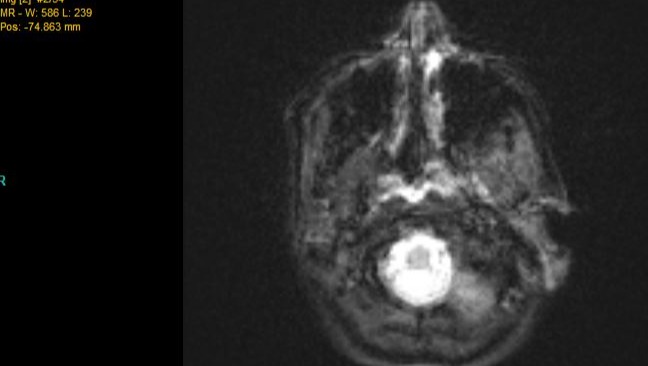

On November 21, 2023, Cassandra was rushed to the hospital after the surgery caused serious complications. During the procedure, the surgeon penetrated her brain, resulting in a bleed. A foreign object, which we believe to be bone wax, was left on her brain, and her health rapidly declined.

The images below are some of her scans and the object on her brain: